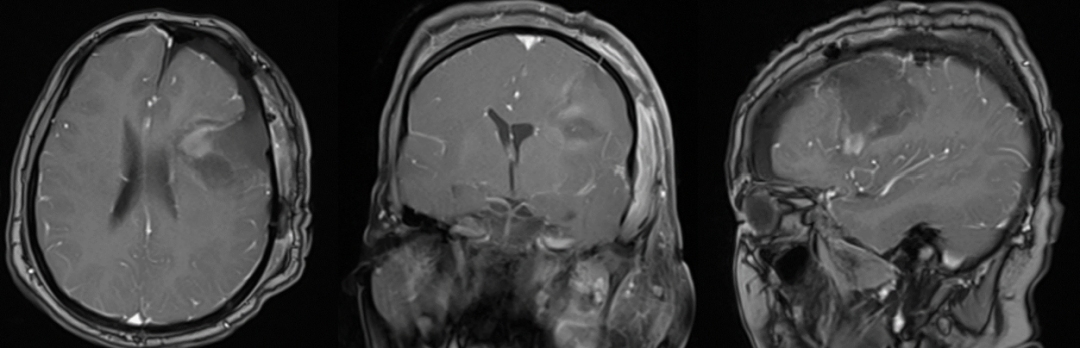

患者女性,38岁,头痛一年余,加重2月入院。

入院查体:患者意识清楚,对答切题,双侧瞳孔等大等圆,双侧瞳孔等大等圆,对光反射正常,四肢活动好,肌力及肌张力正常。头颅磁共振提示左侧额顶部占位,考虑胶质母细胞瘤。

术前磁共振:

术后磁共振:

图39. 术后患者意识清楚,肢体及言语功能活动好,暂出院以待进一步放化疗治疗